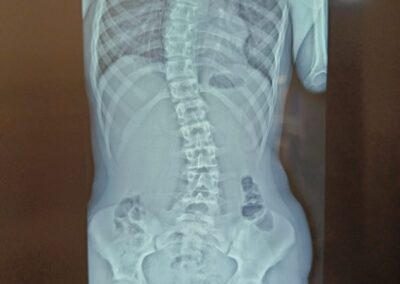

La scoliose est une déviation de la colonne vertébrale dans les 3 plans de l’espace. Celle-ci amène une silhouette asymétrique (visible au niveau des épaules et de la taille) et l’apparition de gibbosités (bosse), ainsi qu’un déséquilibre et une limitation de mouvement du tronc. Dans certains cas graves, la capacité respiratoire du patient peut se trouver limitée.

La scoliose est une pathologie qui se développe souvent pendant l’enfance et évolue progressivement au fil de la croissance. L’évolution est généralement lente dans période prépubère puis connait une accélération au moment de la puberté. Un examen médical est le seul moyen de détecter cette pathologie, les patients atteints ne souffrant en général pas de douleurs dorsales.

Le traitement se fait par appareillage au moyen d’un corset orthopédique sur mesure, moulé sur le corps et conçu de manière à permettre une croissance normale du rachis en corrigeant les déformations existantes.

Chaque corset est réalisé et adapté selon la morphologie du patient. Il tient compte de la déformation du rachis, du poids et de la taille de celui-ci, ainsi que de la prescription médicale. Selon la déformation du rachis et le modèle de corset prescrit, les temps de port de ce dernier peuvent être variables. De même des ajustements peuvent être réalisés selon l’évolution de la pathologie et de la morphologie du patient.